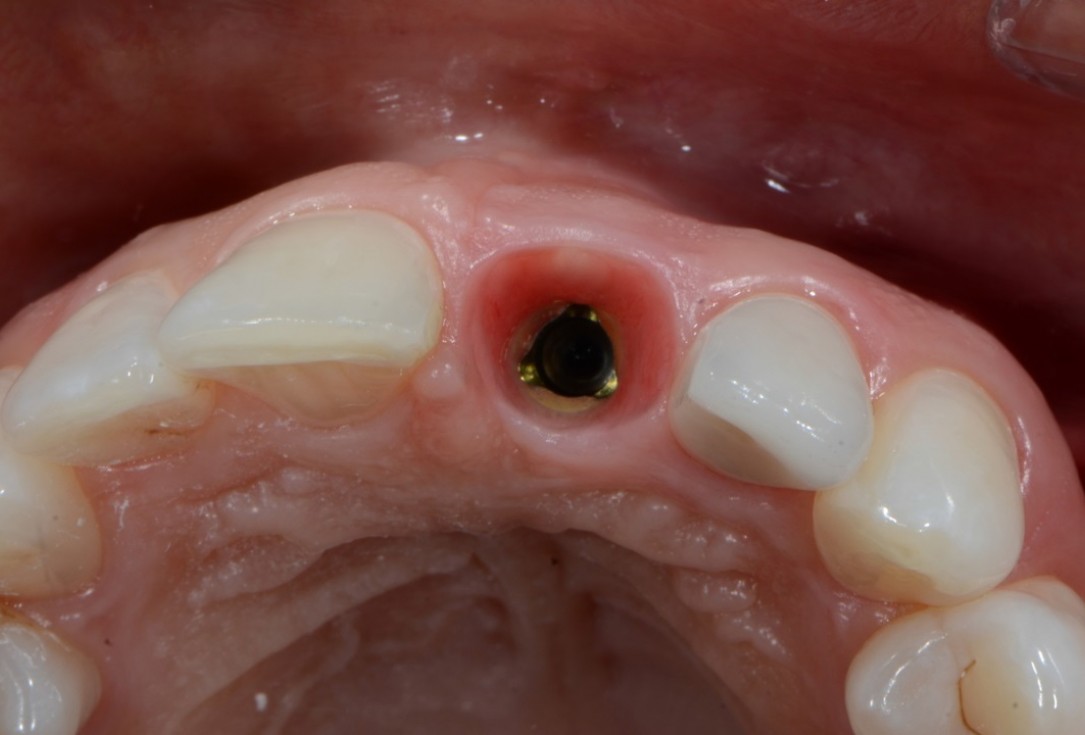

12/16 - Situation after removal of healing cap

Socket preservation with cerabone® - Dr. R. A. Nader